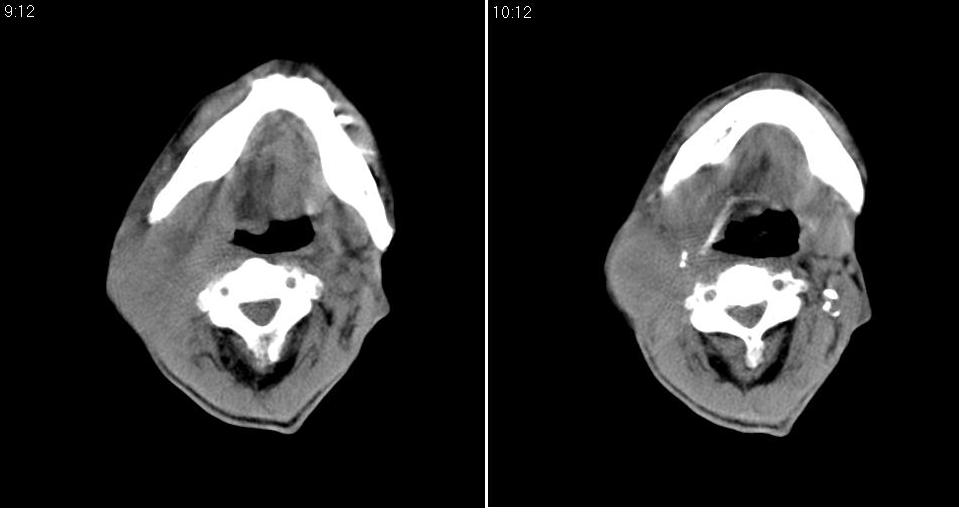

男 70岁,右侧颈部包块八个月余,下午及夜间疼痛加剧,包块质硬。化验穿刺镜下可见大量成堆裸核上皮细胞,可符合结核性淋巴结炎。

右侧颈部不规则软组织密度肿块影,密度均,边缘不清,颈筋膜间隙闭塞,向内致口喉咽受压变形,外达胸锁乳突肌深部,与之分界不清,周围骨质未见异常。

病灶广泛呈浸润性生长,提示恶性病变。楼主已经指明是结核了,谢谢。

病灶广泛呈浸润性生长,与周围组织关系模糊不清,提示恶性病变可能性较大。但楼主已经指明是结核了。